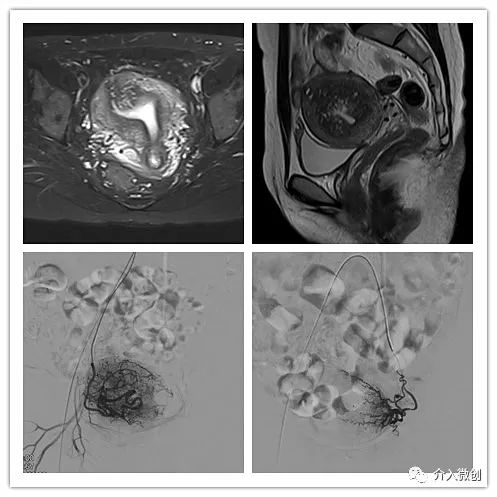

术前子宫MRI提示宫腔明显增大,诊断为子宫腺肌瘤

术后4个月复查,子宫明显缩小,腺肌瘤明显坏死吸收